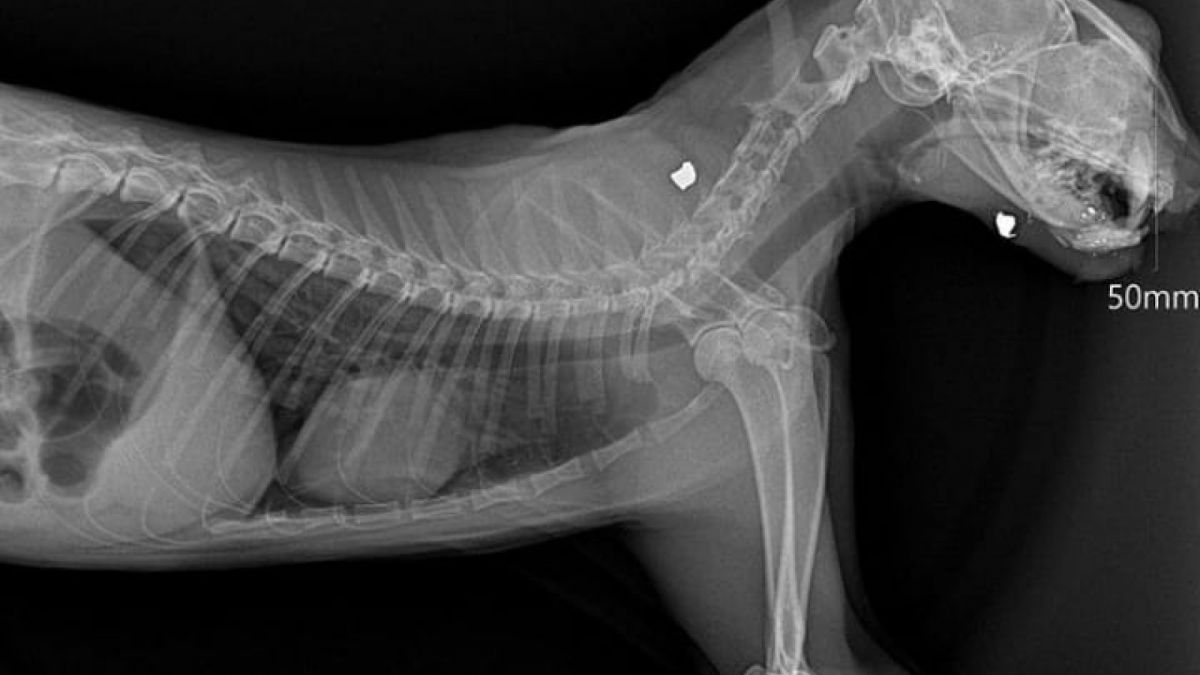

Hasil x-ray kucing yang ditembak di lingkungan sesko TNI Bandung. [Instagram Rumah Singgah Clow]

Dari hasil x-ray, selain ditemukan dua peluru. Satu dari mata tembus ke mulut dan peluru satu lagi di punggung," tulis akun itu.

Satu di antara kucing yang ditembak itu selamat. Kucing ini ditembak di mata dan tembus hingga ke mulut.

"Matanya ditembak dan tembus ke mulut, saat ini dibawa ke @amoreanimalclinic untuk penanganan X-ray dan operasi," lanjutnya.